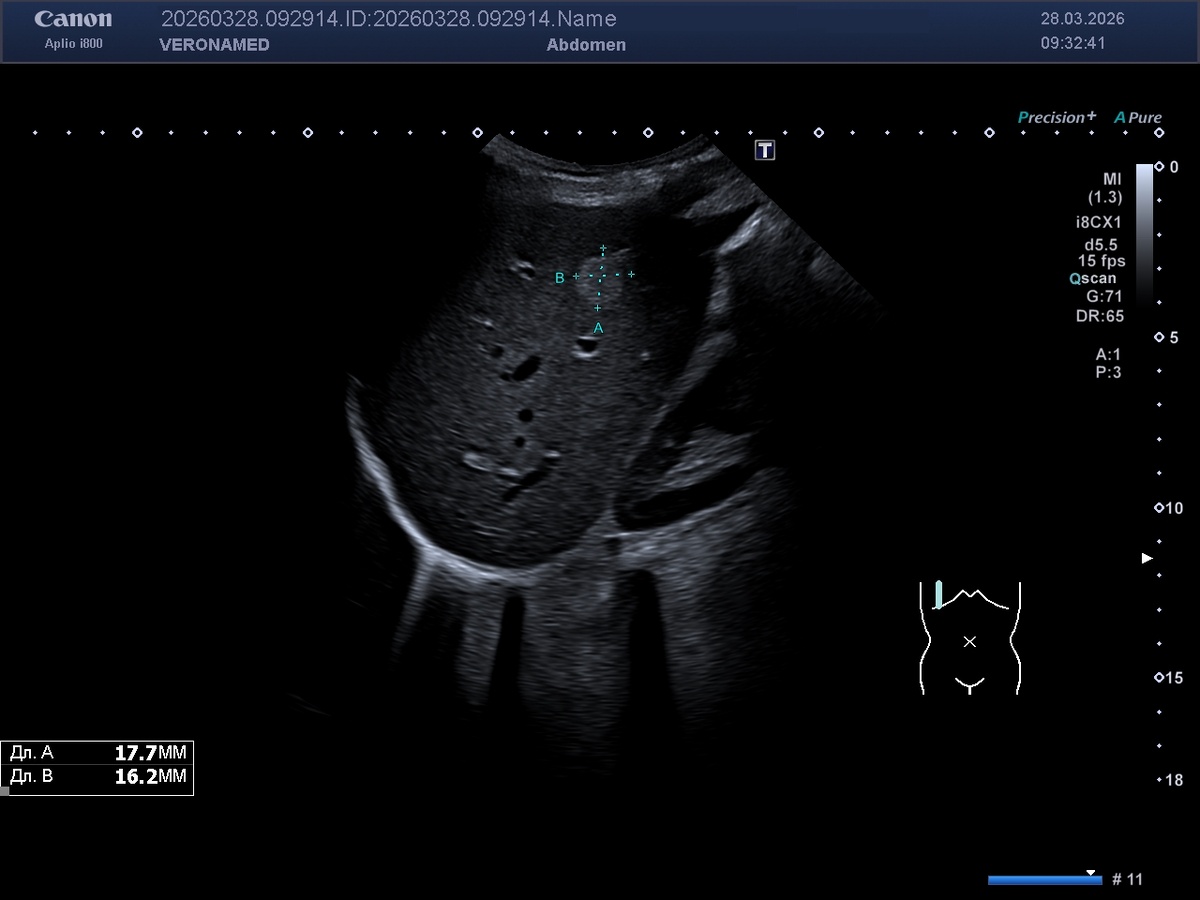

Гемангиома печени — это доброкачественная сосудистая опухоль, которая является наиболее распространенной некистозной опухолью печени. Происхождение гемангиомы печени у людей является сложным и многофакторным процессом, который включает генетические, эмбриологические и гормональные факторы. 1. Эмбриологическое происхождение и сосудистая мальформация

Гемангиомы печени считаются врожденными сосудистыми мальформациями, которые возникают в результате нарушений в развитии кровеносных сосудов во время эмбриогенеза [1]. Эти опухоли представляют собой мезенхимальные образования, состоящие из заполненных кровью сосудистых полостей различного размера, окруженных одним слоем плоских эндотелиальных клеток, поддерживаемых фиброзной соединительной тканью [2]. 2. Генетические факторы